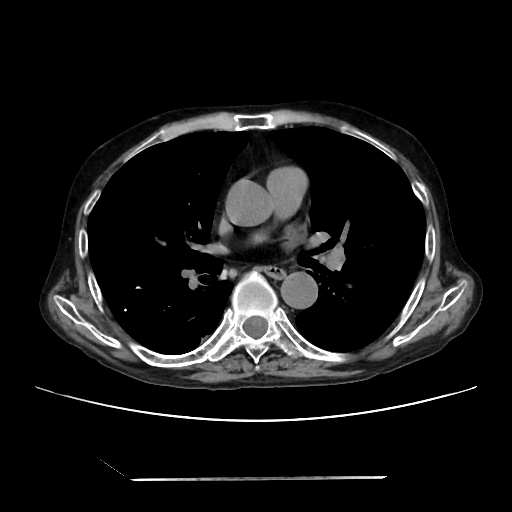

A 58 years old man with....

HRCT done on 17Mar16